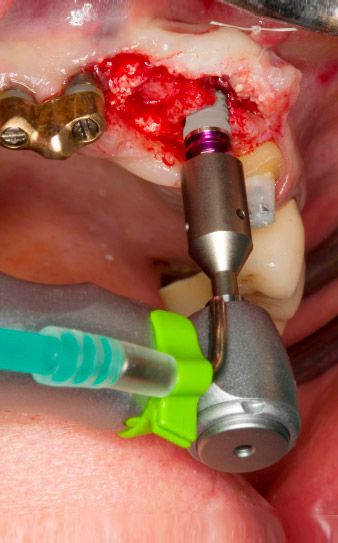

Avvitamento con il manipolo contrangolo WS-75L

Fig. 3: Avvitamento con il manipolo contrangolo WS-75L a una velocità di 20:1 (programma P4). La coppia elevata di Implantmed, con sistema di bloccaggio esagonale per trasmissione di potenza affidabile e inversione automatica della direzione di rotazione al raggiungimento di una resistenza troppo elevata, si è rivelata particolarmente utile in questo caso.

Posizionamento motorizzato dell'impianto

Fig. 4: Posizionamento motorizzato dell'impianto con il manipolo contrangolo WS-75L a una velocità di 20:1 (programma P5).